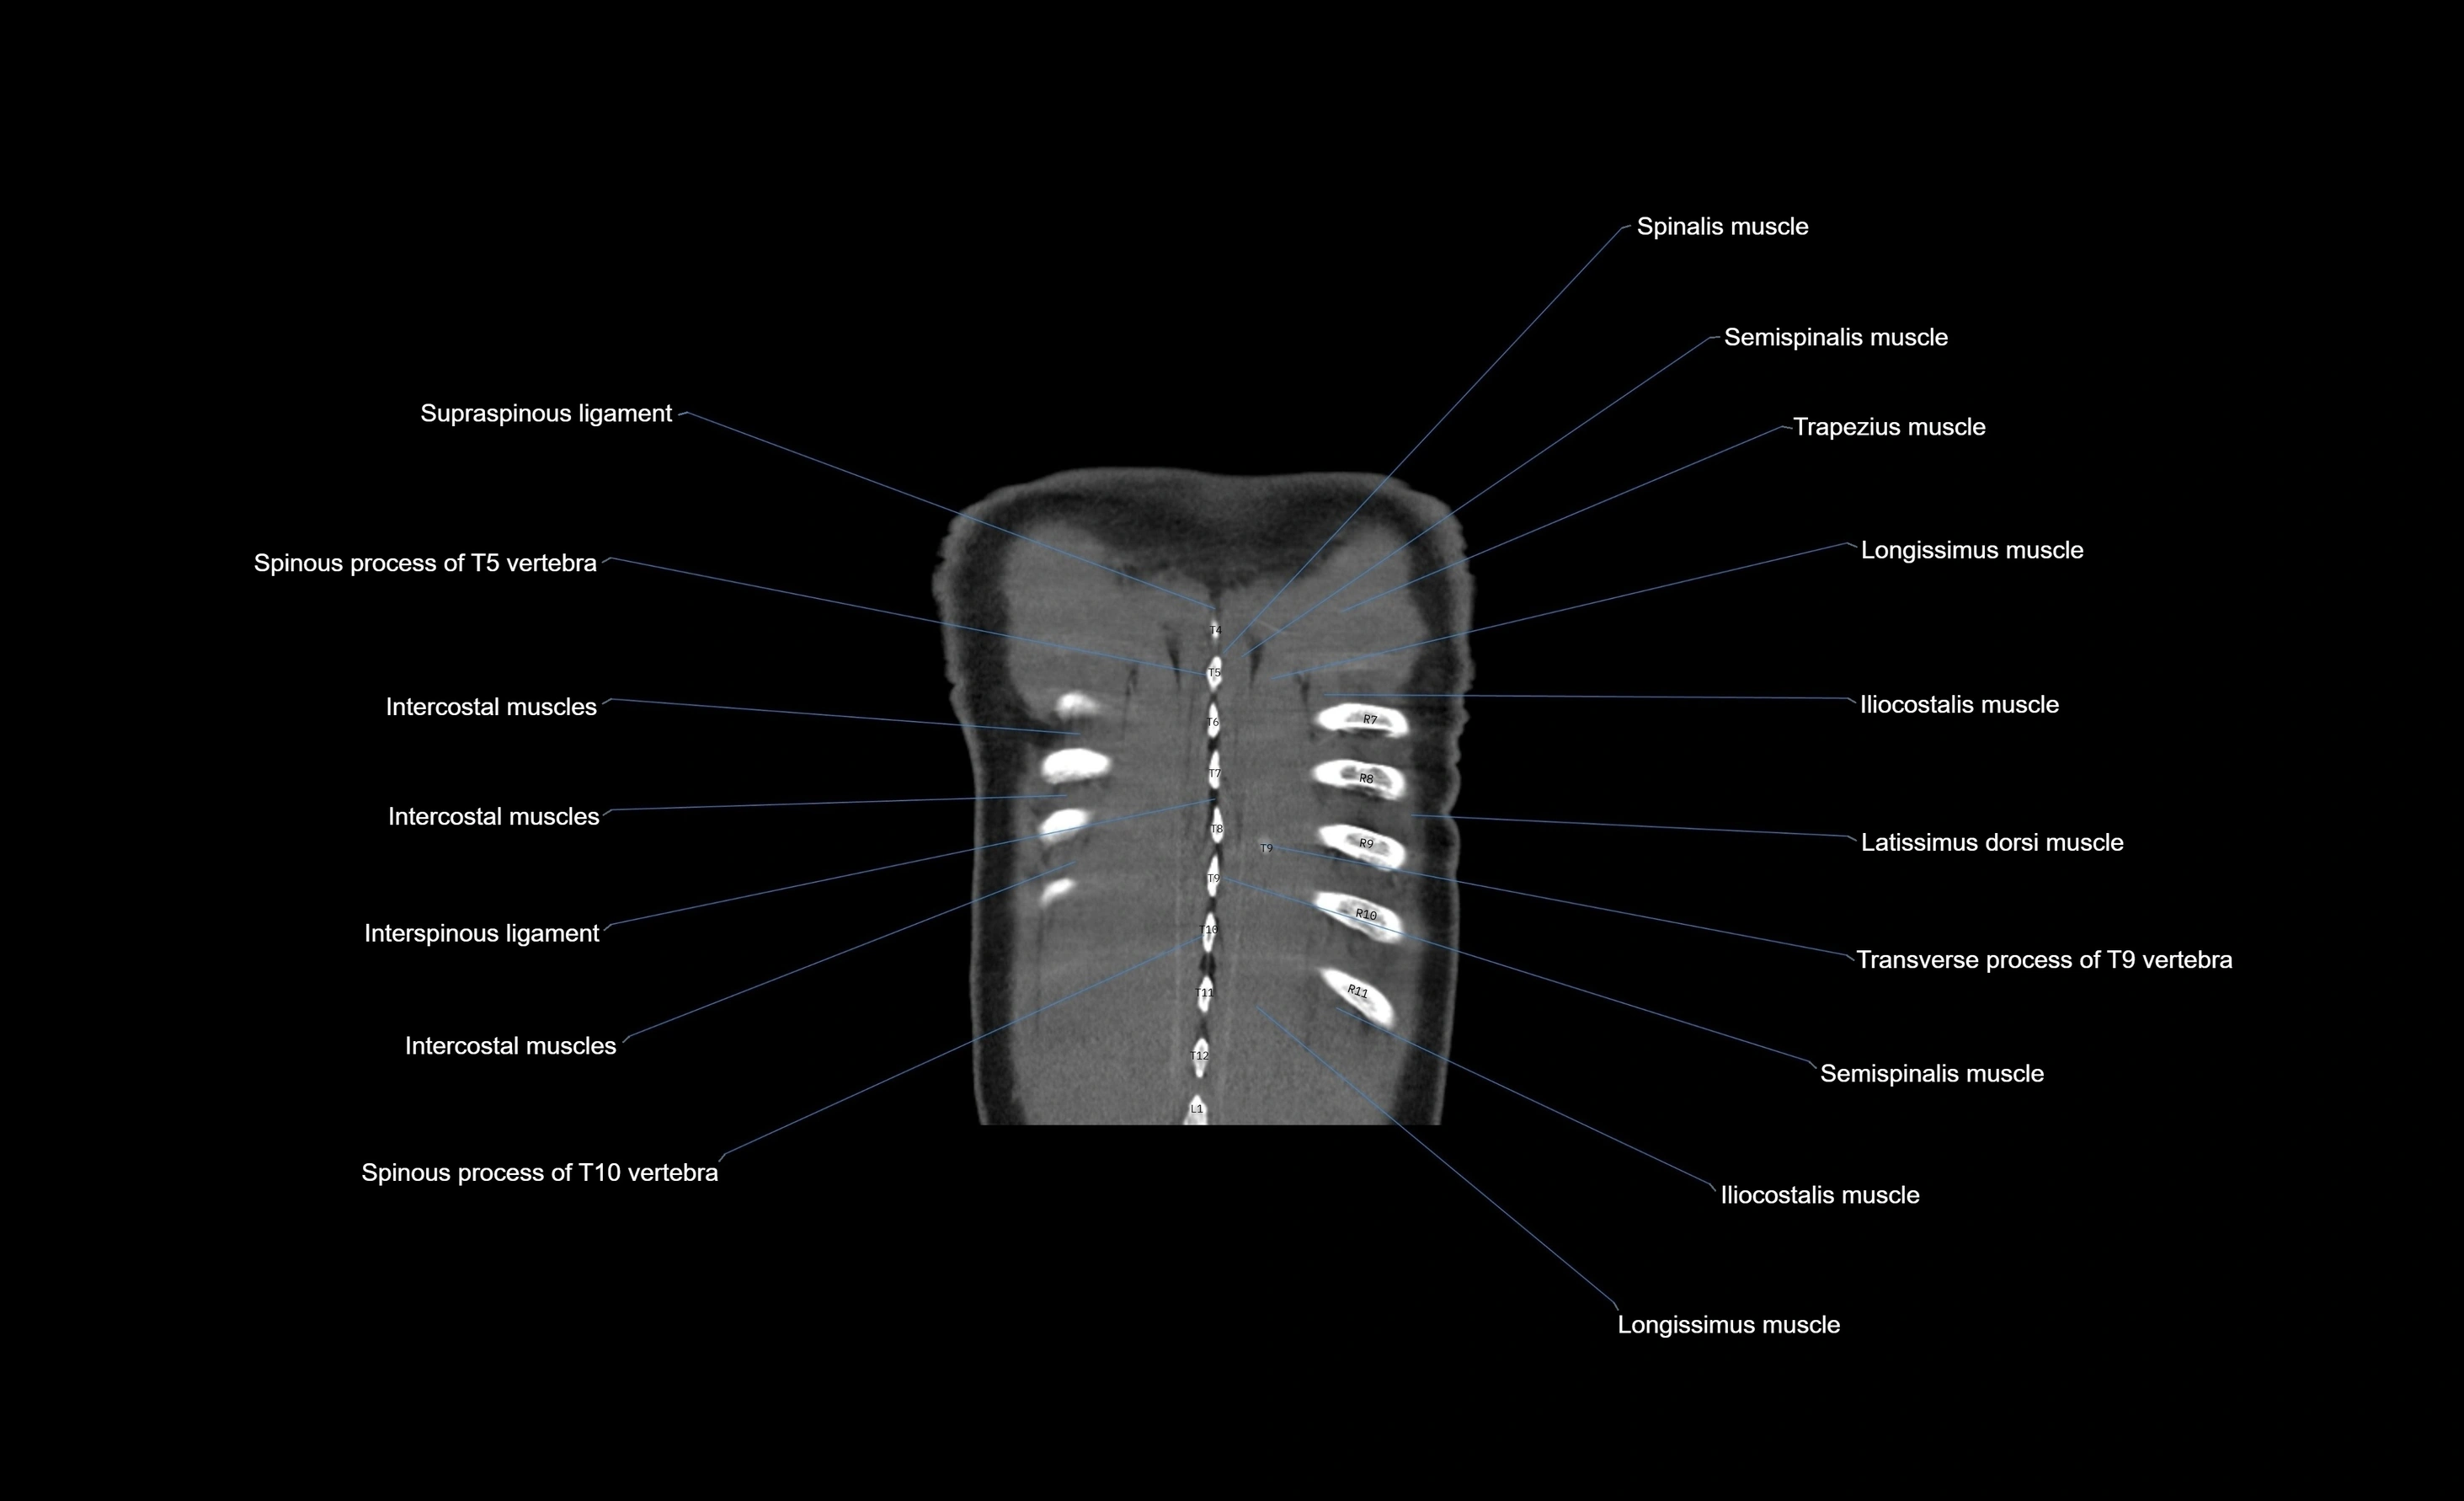

- Erector spinae muscles

- Intercostal muscles

- Interspinous ligament

- Multifidus muscles

- Rhomboid major muscle

- Rhomboid minor muscle

- Serratus posterior superior muscle

- Spinous process of vertebra

- Trapezius muscle